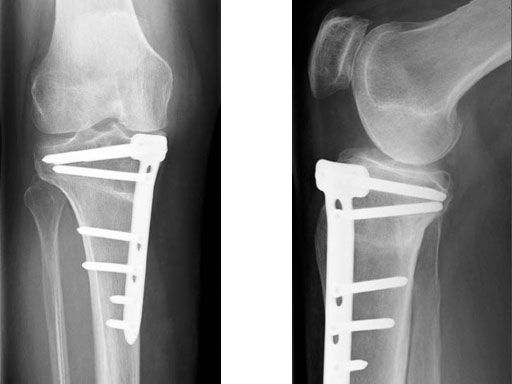

A 68-year-old female.

Case provided by Alex Staubli, Luzern, CH

The patient is mobilized on crutches on day one after surgery. Partial weight bearing is allowed from the beginning. Biomechanical and RSA studies have proven that postoperative loading of the implant by body weight in standard partial weight bearing and early full weightbearing conditions did not cause loss of correction. Our group now allows the patients to walk without crutches as soon as the postoperative pain allows after this type of surgery. Members of the Knee Expert Group (KNEG) have presently implanted over 1,500 TomoFix medial tibia. The results are extremely positive in respect to osteotomy healing, implant failure, and surgical complications.